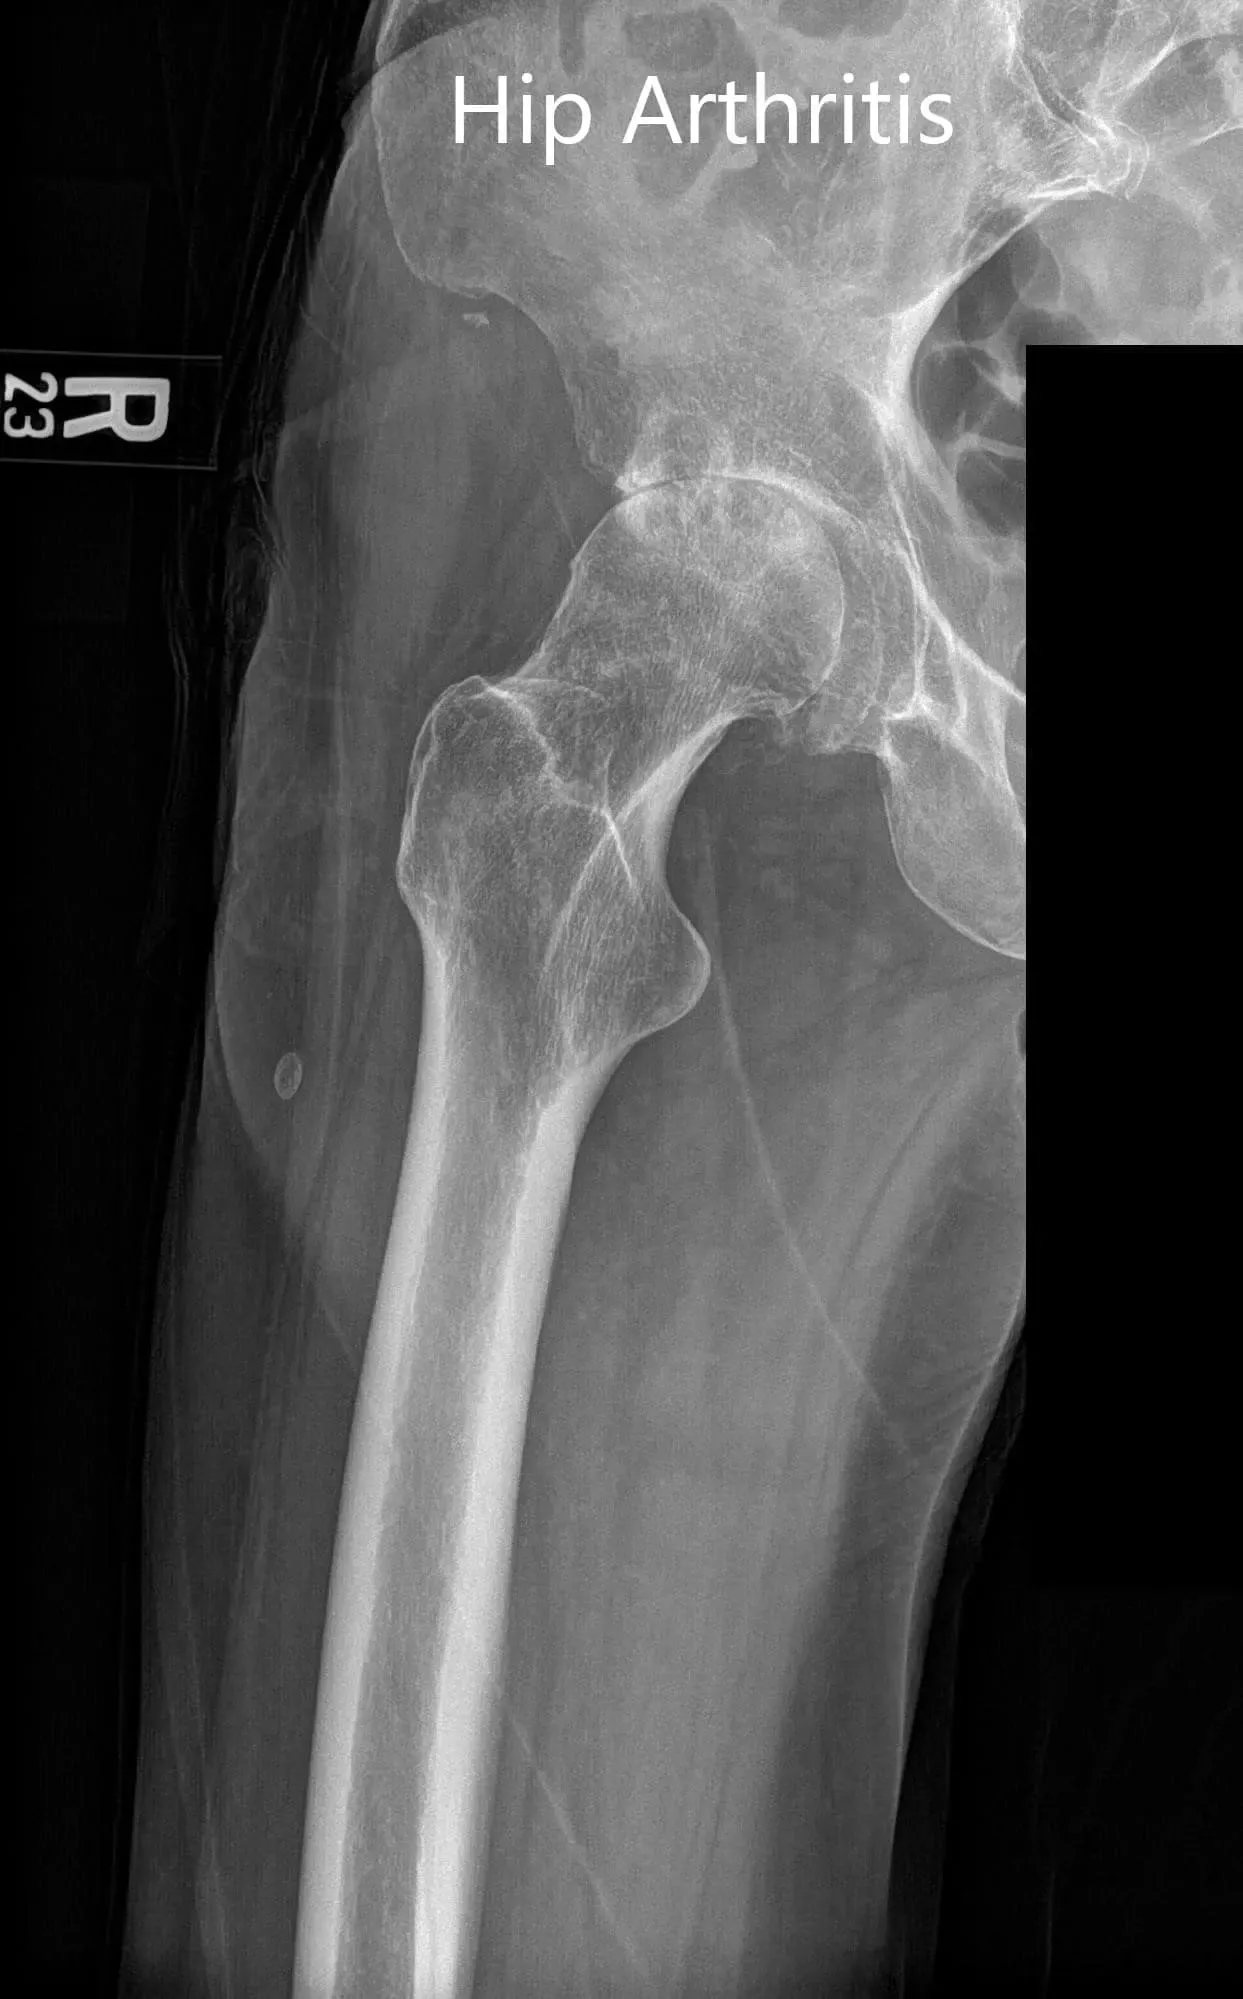

Imaging revealed osteoarthritic changes in bilateral hips (right greater than left). Considering the patient’s comorbidities and lifestyle limiting hip arthritis, he was advised bilateral total hip replacement. Risks, benefits, and alternatives were discussed with the patient at length. He decided to go for right hip replacement first.

Preoperative AP and lateral views of the right hip joint.